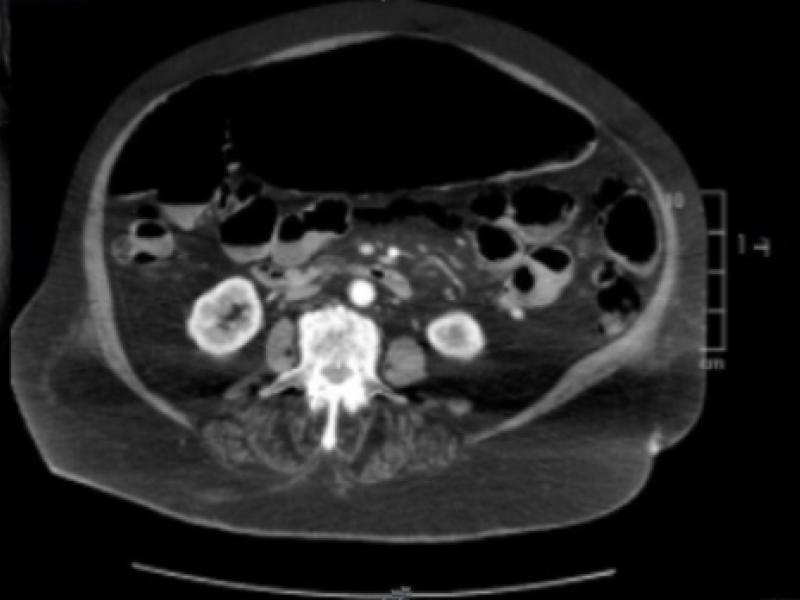

What's the Diagnosis? By Dr. Abby Renko